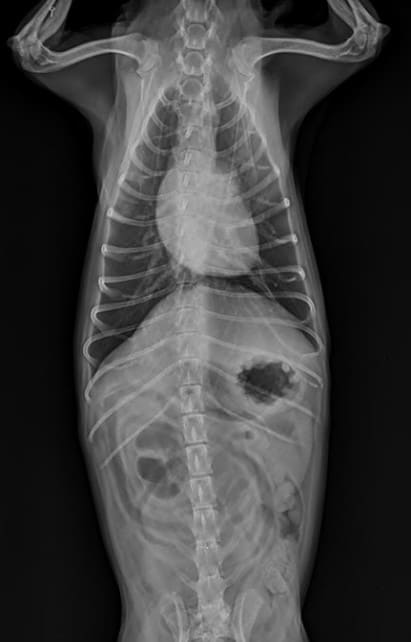

반려견 기흉은 흉강 내에 공기가 비정상적으로 축적되는 응급 질환입니다. 정상적인 상태에서 폐는 흉강 내에서 음압을 유지하며 팽창과 수축을 반복하는데, 기흉이 발생하면 이러한 음압 상태가 깨지면서 폐가 제대로 팽창하지 못하게 됩니다. 이는 반려견의 호흡 기능에 심각한 영향을 미치며, 적절한 치료를 받지 못할 경우 생명을 위협할 수 있는 상황으로 발전할 수 있습니다. 기흉의 발생 원인은 크게 외상성과 자발성으로 나뉘며, 교통사고나 높은 곳에서의 낙상, 다른 동물과의 싸움 등으로 인한 외부 충격이 가장 흔한 원인입니다. 또한 폐 조직 자체의 문제나 기존에 앓고 있던 호흡기 질환의 합병증으로도 발생할 수 있습니다. 특히 노령견이나 만성 기관지염을 앓고 있는 반려견의 경우 폐포가 약해져 있어 기흉 발생 위험이 더 높습니다. 반려견 기흉 증상을 조기에 발견하는 것은 매우 중요한데, 초기 단계에서는 증상이 경미하여 보호자가 놓치기 쉽지만, 시간이 지날수록 호흡 곤란이 심해지고 생명이 위험해질 수 있기 때문입니다. 따라서 보호자는 평소 반려견의 호흡 패턴과 활동량을 주의 깊게 관찰하고, 이상 징후가 보이면 즉시 동물병원을 방문해야 합니다.